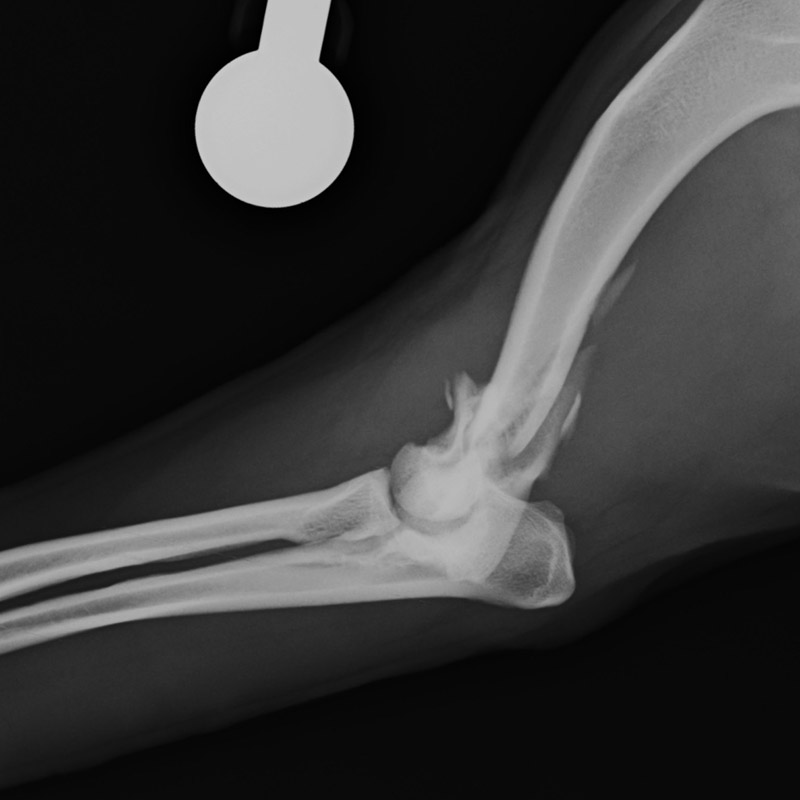

肘関節内骨折

アメリカン・コッカー・スパニエル(5歳)

車の窓から落下

手術前

手術後